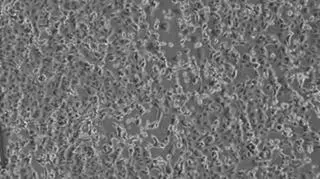

Zdjęcie wyizolowanego koronawirusa 2019-nCoV/Italy-INMI1 (PAP/EPA/INMI SPALLANZANI HOSPITAL PRESS OFFICE HANDOUT)

Źródło: PAP/EPA/INMI SPALLANZANI HOSPITAL PRESS OFFICE HANDOUT